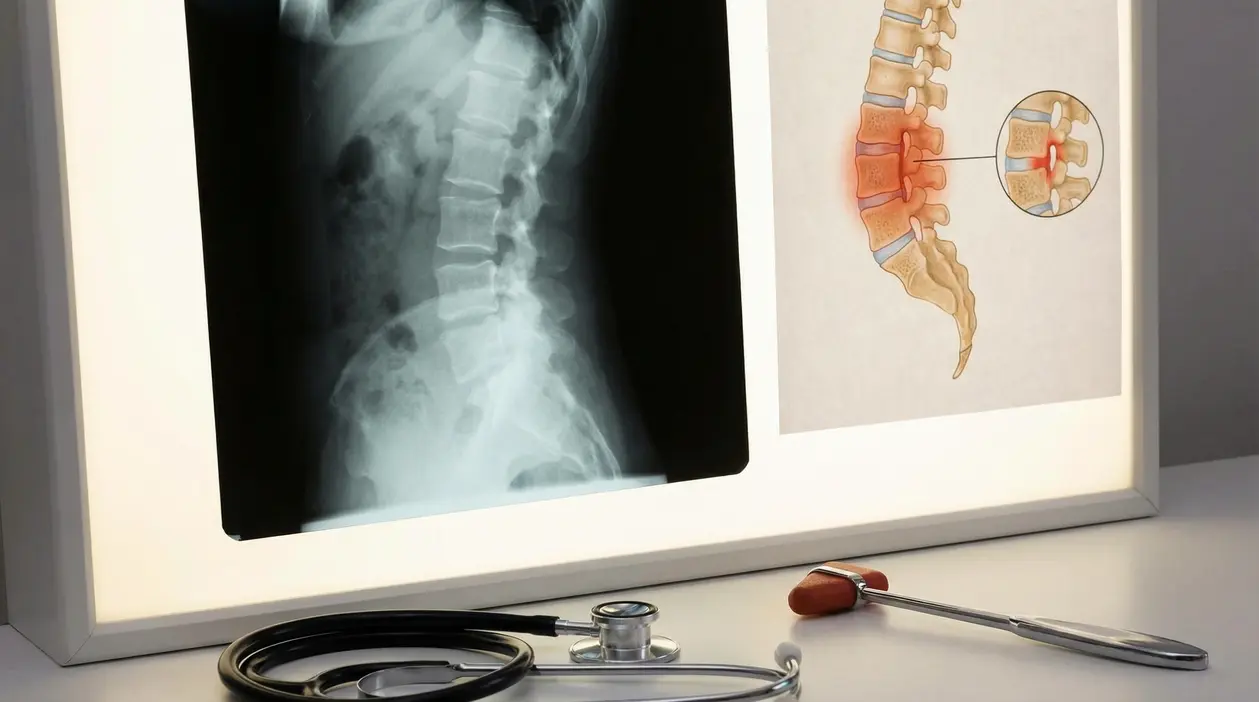

Imaging: la svolta tra radiografia e risonanza

Il punto chiave spesso è vedere cosa succede alle sacro-iliache.

- La radiografia può mostrare una sacroileite “già evidente”, ma tende a essere meno sensibile nelle fasi iniziali.

- La risonanza magnetica (RM) è preziosa quando la malattia è ancora “non radiografica”, perché può evidenziare infiammazione precoce.

Nella pratica clinica si usano criteri come ASAS (e anche ESSG), che combinano segni clinici, imaging e dati di laboratorio. Qui la parola utile da ricordare è sacroileite, perché è uno dei reperti più caratteristici.